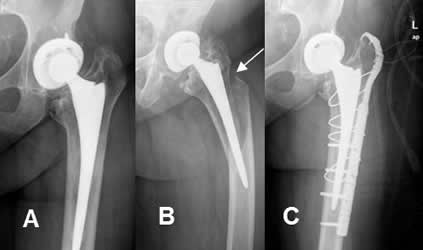

Fig 119. Fractura periprotésica.

A: Rx AP. Prótesis en la cabeza femoral.

B: Rx AP. Fractura oblicua y subtrocantérica, con angulación en varo.

C: Rx AP. Fijación de la nueva lesión con placa y cerclaje.